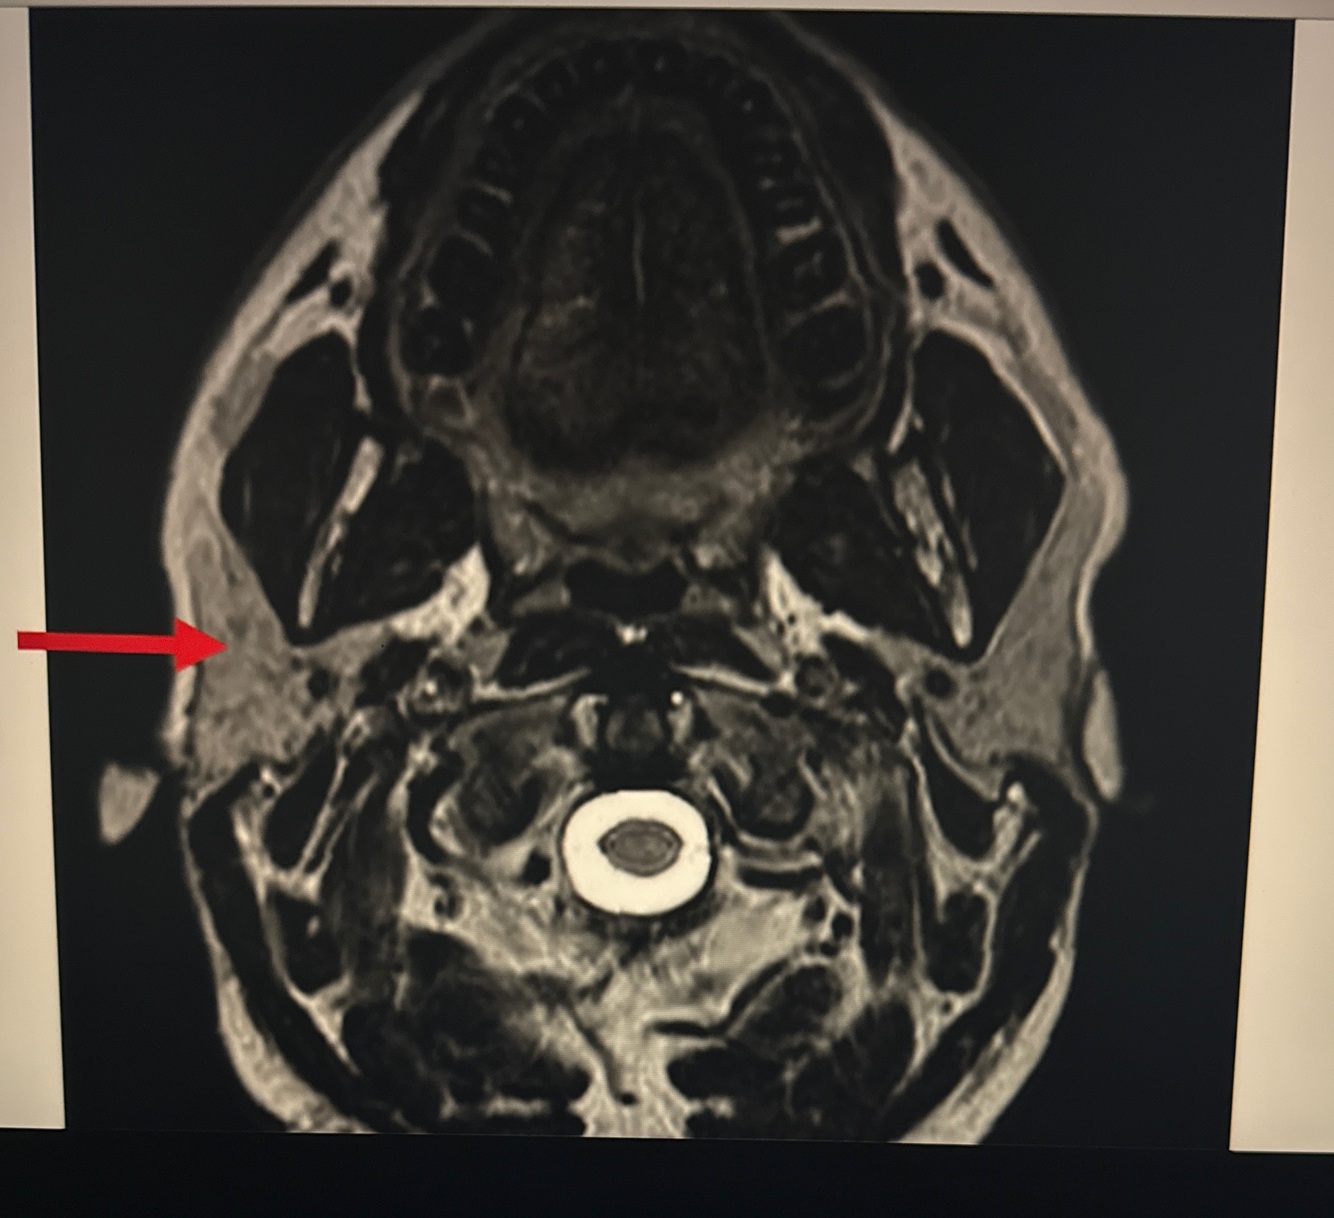

Q

A. Fat

B. Submandibular gland

C. Parotid gland

D.Sternocleidomastoid

A

C. Parotid